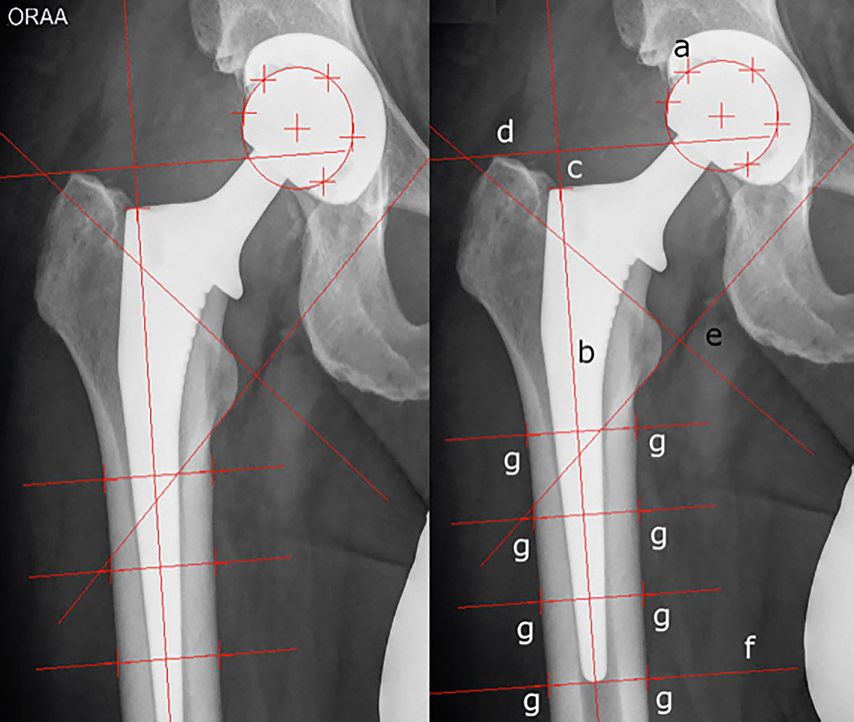

Im Vergleich zu EBRA-Cup bietet EBRA-FCA (Femoral Component Analysis) die Möglichkeit, die Migration des Schaftes in longitudinaler Richtung (Absinken des Schaftes, „subsidence“) zu erheben.9,10 Aufgrund der Anatomie des Femurschaftes stellt dies den wesentlichen Migrationsparameter des Schaftes dar.10 Hierfür ist zunächst die Bestimmung der Schaftachse erforderlich. Anschließend erfolgt die Markierung von Prothesenkopf, Prothesenschulter, Trochanter major und minor sowie der Femurkontur mit weiteren Referenzpunkten (Abb.2).9

Abb. 2: Migrationsanalyse des Schaftes mit EBRA-FCA: a) Markierung des Prothesenkopfes, b) Schaftachse, c) Prothesenschulter, d) Tangente am Trochanter major, e) Tangenten am Trochanter minor, f) Tangente an der Prothesenspitze, g) Markierung der Femurkontur